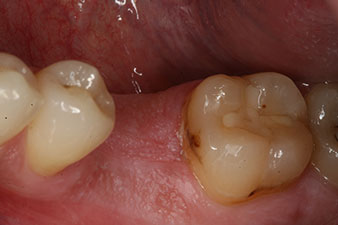

отпечатък

Фиг. 8: Взет е отпечатък за окончателната корона.

Следователно, успешната остеоинтеграция и адекватната биологична стабилност могат да бъдат записани, което даде възможност да се вземе отпечатък в една и съща сесия.

Последните снимки показват закрепената с винт монолитна композитна корона на място и рентгеновата проверка (фиг. 9 и 10) (6).